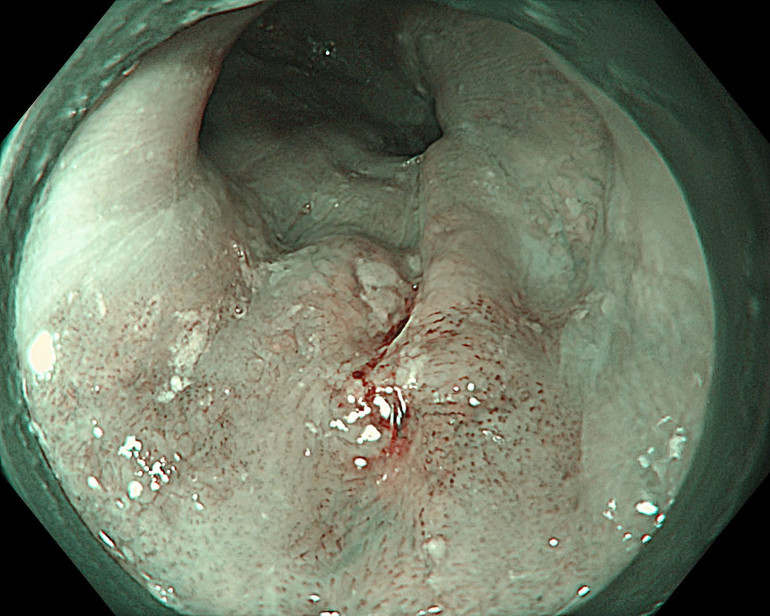

Hình ảnh thực quản tổn thương được phát hiện qua hệ thống nội soi thế hệ mới.

Mới đây, một bệnh nhân nam 63 tuổi, tiền sử hút thuốc lá nhiều năm khi nhập viện đã được chỉ định nội soi tiêu hóa trên trong chương trình khám sức khỏe định kỳ. Quá trình tầm soát ung thư vùng họng-thực quản được thực hiện bằng công nghệ NBI ngay từ khoang miệng, hạ họng-thanh quản đến toàn bộ thực quản. Nội soi phóng đại với hệ thống Olympus X1 và dây soi EZ1500 cho phép quan sát rõ vi mạch bề mặt đã phát hiện tổn thương gợi ý ung thư biểu mô vảy thực quản giai đoạn sớm ở lớp niêm mạc, có chỉ định điều trị bằng cắt tách dưới niêm mạc qua nội soi (ESD). Đây là phương pháp can thiệp tối thiểu, nhằm hạn chế xâm lấn, giúp tiết kiệm chi phí, đồng thời cải thiện thời gian sống và chất lượng cuộc sống của người bệnh. Sau can thiệp ESD, bệnh nhân hồi phục tốt và xuất viện sau 2 ngày.

Một bệnh nhân nam 67 tuổi, tiền sử nghiện rượu và hút thuốc lá khi sử dụng hệ thống nội soi Olympus EVIS X1 với công nghệ NBI phát hiện một tổn thương kích thước khoảng 10mm tại thực quản. Dựa trên hình ảnh nội soi và kinh nghiệm chuyên môn trong đánh giá ung thư sớm, các bác sĩ xác định tổn thương đã vượt quá chỉ định điều trị qua nội soi và được khuyến cáo phẫu thuật. Sau phẫu thuật, kết quả mô bệnh học xác định ung thư biểu mô thực quản đã xâm lấn vào lớp dưới niêm mạc, không phù hợp với các phương pháp can thiệp nội soi.